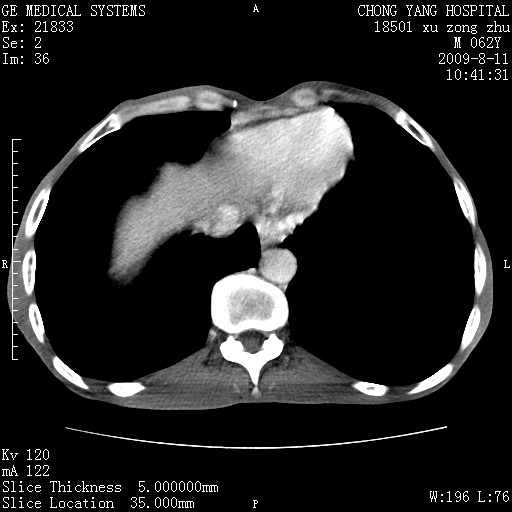

以下是引用杀毒软件在2009-8-11 16:35:00的发言:[br]肝内胆管扩张局限于左叶,胆管内有结石伴肝外胆管结石,胆管壁增厚呈弥漫性并发腹腔积液,胰腺边界模糊。[br][br]考虑---胆总管及肝内胆管结石继发胆管炎及胰腺炎,左肾下极囊肿,腹水。

以下是引用zjzjr在2009-8-11 17:35:00的发言:[br]肝内胆管扩张局限于左叶,胆管内有结石伴肝外胆管结石,胆管壁增厚呈弥漫性并发腹腔积液。[br][br]考虑---胆总管及肝内胆管结石继发胆管炎,左肾下极囊肿,腹水。